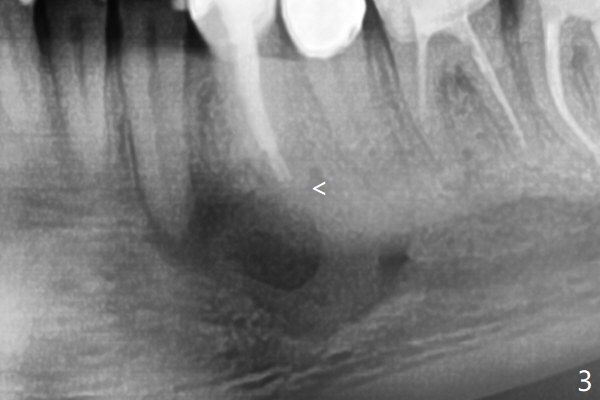

术前冷和电牙髓活力测定显示左下3活髓,不得不做一个长切口和附加切口(图二:>),在暴露颏神经后,在4根尖做囊肿切除术(图一),好像上颌窦外提升,使用上颌窦提升术器械才把囊肿挖出来,不同之处是颊侧骨壁特别厚,为了容易去除4根尖舌侧囊肿,做了根切(图三:<,与图三 ' (术前)对比),但是没做倒充,觉得根管充填完整。并且填入不少粘性骨块(图三)。病理报告:Left Mandibular Body, #21, Excisional Biopsy: Benign fibrous and granulation tissue with acute and chronic inflammation, consistent with periapical granuloma. Negative for odontogenic keratocyst and unicystic ameloblastoma. 左下颌骨体部,21号牙,切除性活检:良性纤维和肉芽组织伴有急性和慢性炎症,与根尖周围肉芽肿一致。牙源性角化囊肿和单房性造釉细胞阴性。术后两个月伤口愈合(图四),骨粉好像安居乐业(图五:*)。